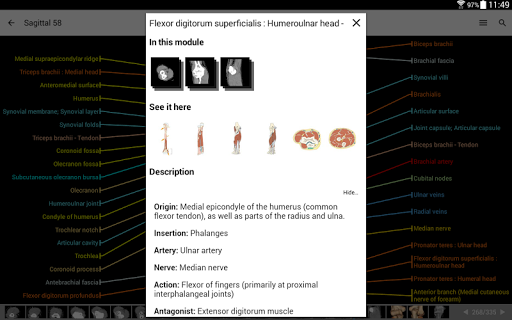

IMAIOS e-Anatomy adalah atlas anatomi manusia untuk dokter, ahli radiologi, mahasiswa kedokteran, dan teknisi radiologi. Dapatkan cuplikan lebih dari 26.000 gambar medis dan anatomi secara gratis sebelum berlangganan atlas anatomi manusia terperinci kami.

e-Anatomy memiliki lebih dari 26.000 gambar yang berisi serangkaian gambar dalam tampilan aksial, koronal, dan sagital serta radiografi, angiografi, gambar diseksi, bagan anatomi, dan ilustrasi. Semua gambar medis diberi label dengan cermat, lebih dari 967.000 label tersedia dalam 12 bahasa termasuk Terminologia Anatomica Latin.

- Ketuk label untuk menampilkan struktur anatomi